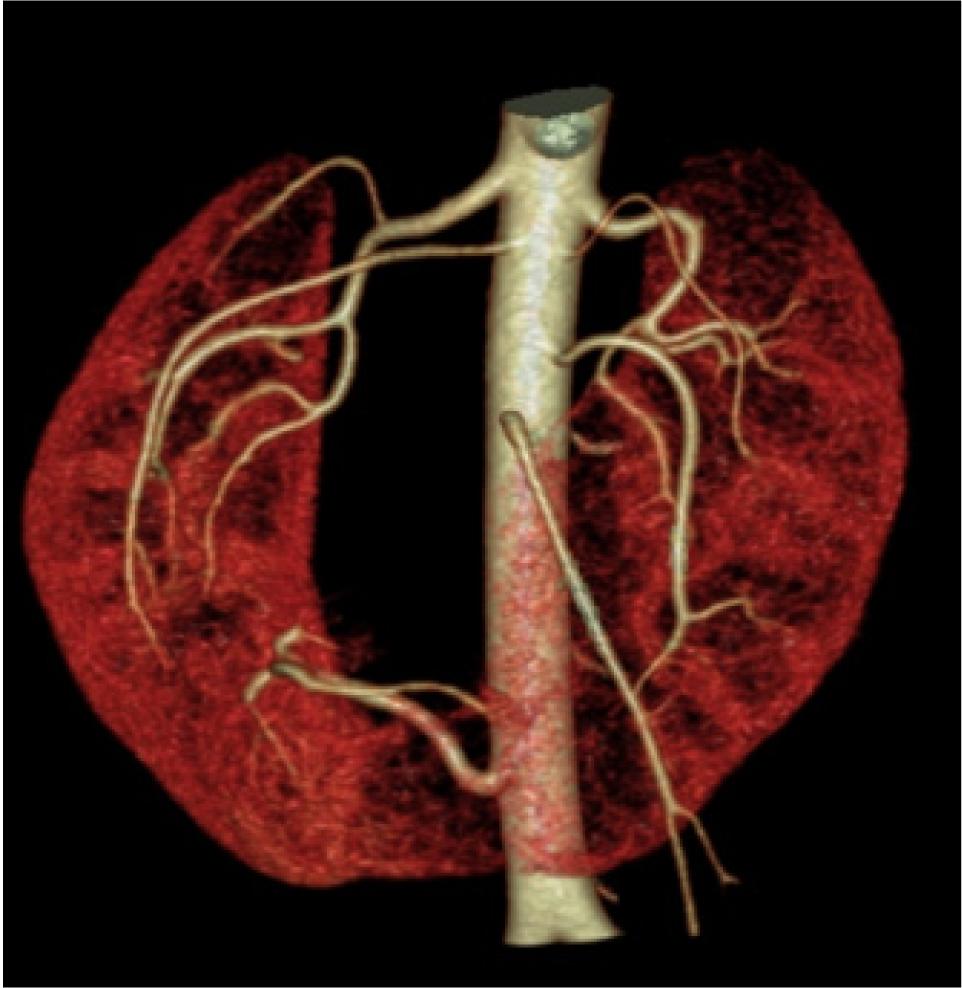

The pancreatic head was compressed and displaced anteriorly; posteriorly mass effect was noted on anterior surface of inferior vena cava with obliteration of intervening fat plane. IVC as a result was compressed and flattened anteroposteriorly (Figure 4).

Figure 4: (A–D) Contrast enhanced CT sagittal images—Mass arising from the isthmus, posteriorly compressing the IVC with obliteration of intervening fat planes (arrow).

Furthermore, the patient was subjected to CT renal angiography which revealed one main renal artery showing hilar branching supplying right upper and interpolar region, and right accessory renal artery supplying interpolar and lower polar region. Left main renal artery showed hilar branching supplying the left interpolar and lower polar region. Out of the two left renal accessory arteries, one artery supplied the left interpolar and lower polar region and the other artery supplied the left upper pole. Another artery arising from infra renal abdominal aorta on the right side at the level of third lumbar vertebra trifurcated the medial branch that supplied isthmus, middle branch that supplied tumor, and lateral branch that supplied the right kidney (Figure 5). Patient could not afford PET-CT, and TNM staging revealed PT1bN0M0 Stage 1.

Figure 5: Three-dimensional volume rendering CT angiography showing renal and accessory arteries on either sides supplying both kidneys. Another artery arising from infra renal aorta supplying isthmus, tumor, and adjoining lower pole of right kidney.